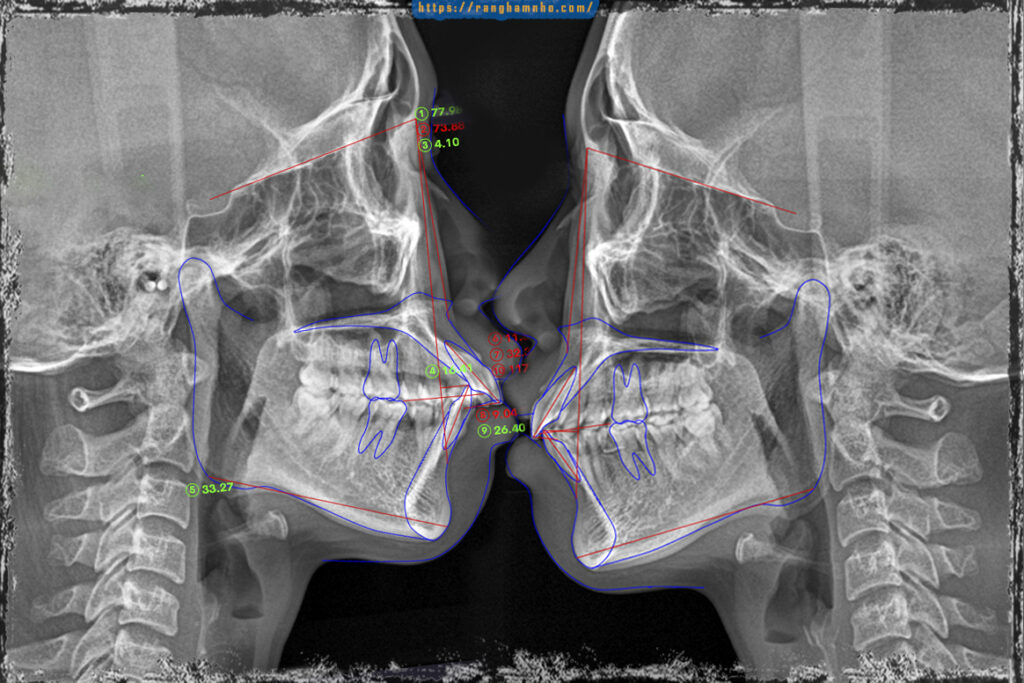

BN sinh năm 1987, đến phòng khám với than phiền hô, nụ cười khấp khểnh, răng chen chúc nhiều. Qua thăm khám đây là một trường hợp hô khá nặng kết hợp cả hô do răng và hô do xương. Nếu mong muốn cải thiện 100% thì BN cần phẫu thuật, cài thiện sau niềng răng đơn thuần chỉ đạt 60-70%.

BN chọn niềng răng đơn thuần với chỉ định nhổ 4 răng số 4, có neo chặn hỗ trợ bằng 2 minivis ở hàm trên.